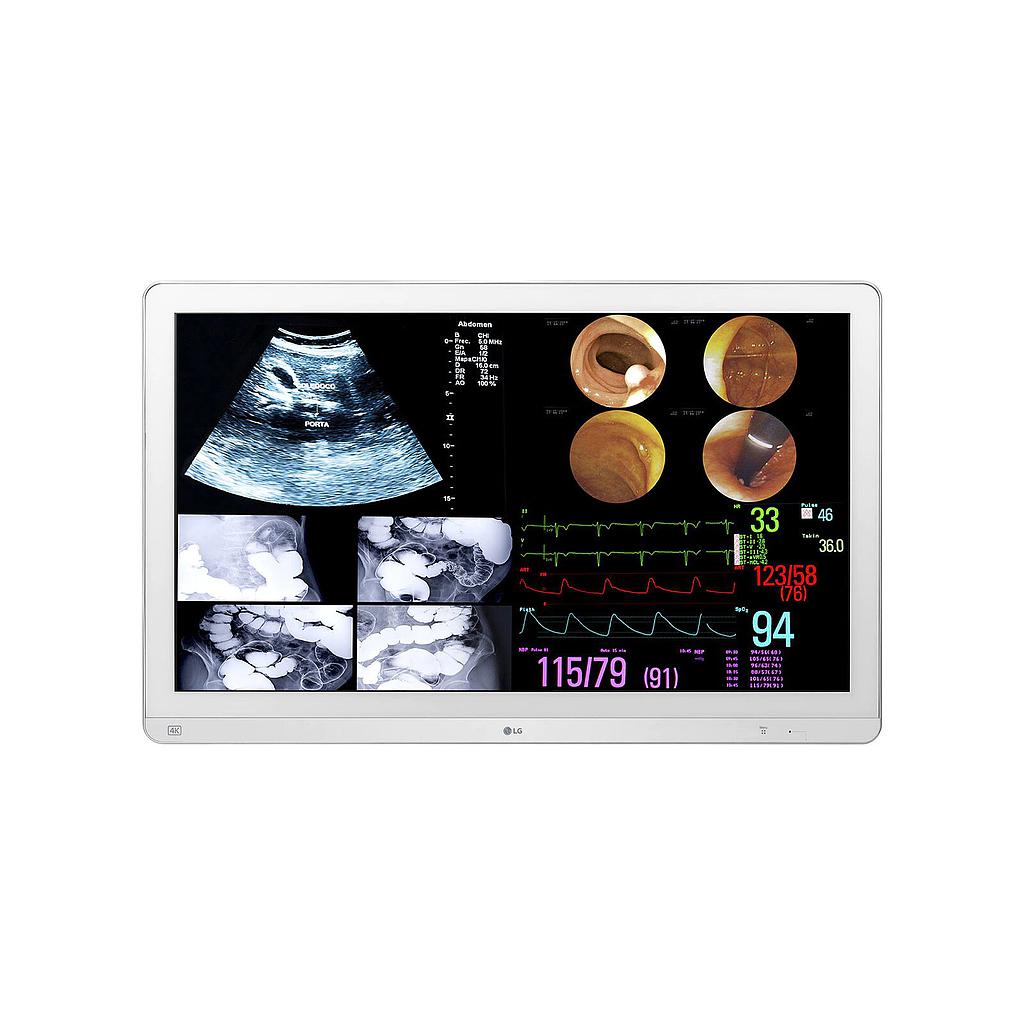

32HL714S-W Monitor Quirúrgico 32" 8MP

Resolución 8MP

Alta resolución 3840 x 2160 px

para una mejor calidad de imagen.

HDR 10

Colores más vivos y mejor

contraste con HDR10.

True Color Pro

Ajusta automáticamente la

configuración de color a los valores

predeterminados por el usuario.

Amplio ángulo de visión

178° de ángulo de visión vertical

y horizontal gracias al uso del

panel IPS.

Certificación IEC 60601

Cumplimiento de los requisitos

de seguridad y funcionamiento

eléctricos básicos.